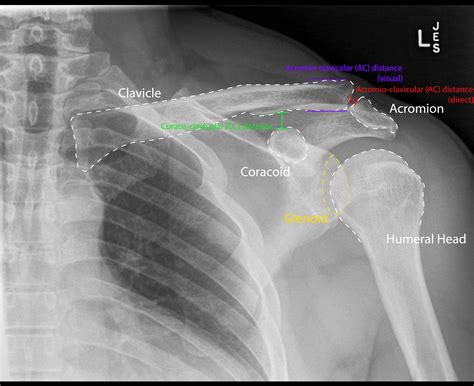

Interpreting the results of an Ac Joint X Ray requires a trained eye. Radiologists look for specific signs and abnormalities that indicate various conditions. Here are some key points they consider:

• Joint Space: The space between the clavicle and scapula should be uniform. Any narrowing or widening can indicate injury or degeneration.

• Bone Alignment: The bones should be properly aligned. Any displacement or misalignment can suggest a fracture or dislocation.

• Bone Density: Changes in bone density can indicate conditions like osteoporosis or bone tumors.

• Soft Tissue: While X-rays primarily show bones, they can also reveal some soft tissue abnormalities, such as swelling or calcification.